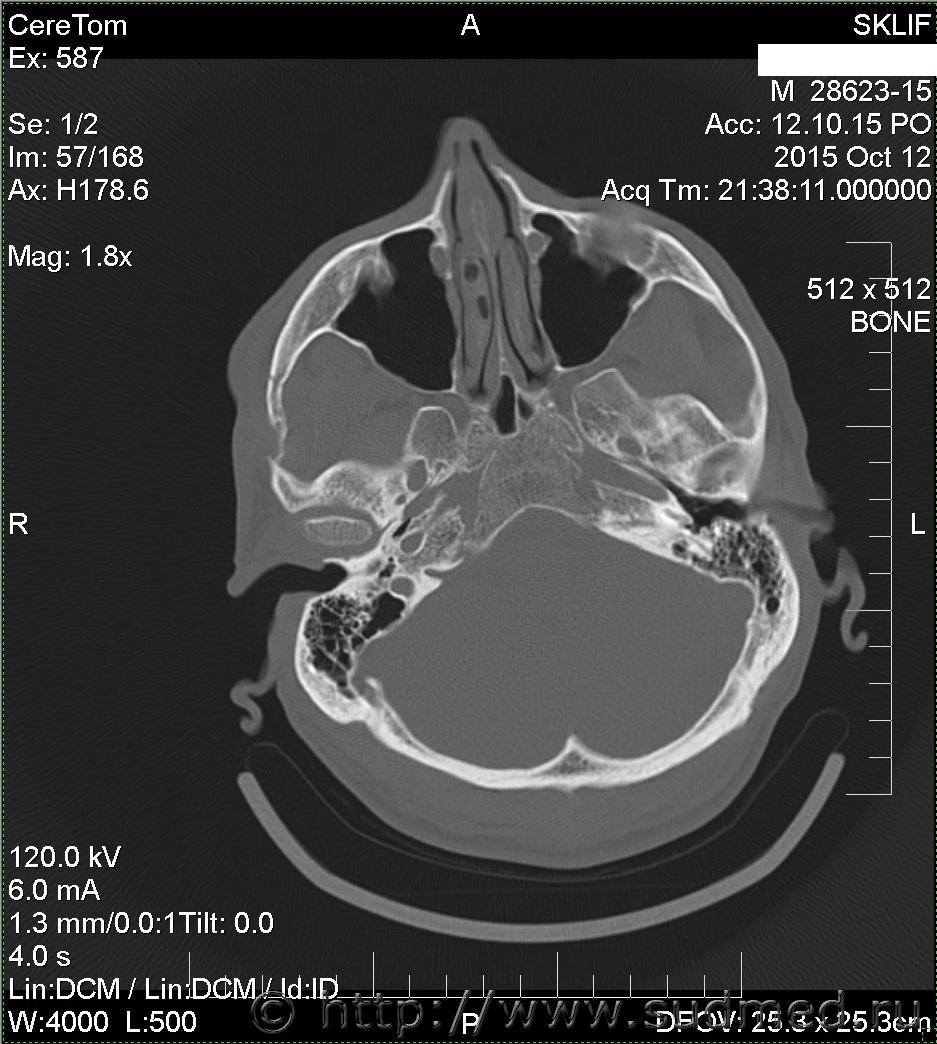

На Ленинградском вокзале меня избил охранник. Что-то я не то ему сказал, что-то он не то понял. В результате у меня множественный перелом скуловой дуги со смещением справа. Я инвалид 2 гр. Больничный не брал.

множественный перелом скуловой дуги со смещением справа

Вред здоровью средней тяжести. В соотвествие сп.7.1 приложения к Приказу Минздравсоцразвития от 24.04.08г. №194н.